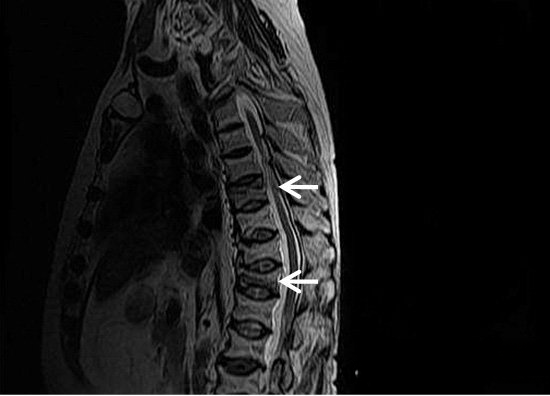

9e5a208ed129c1fe971350d197fcfb2c.gif

图-3放射治疗。轴位T1像显示一个恶性软组织肿块,股骨内为脂肪性骨髓。与对侧股骨内正常的低信号红骨髓进行比较。

ee9f4e632e55619b52cdb7659aafc55c.gif

图-4T1像显示上胸椎因放射治疗而出现的脂肪性骨髓改变。